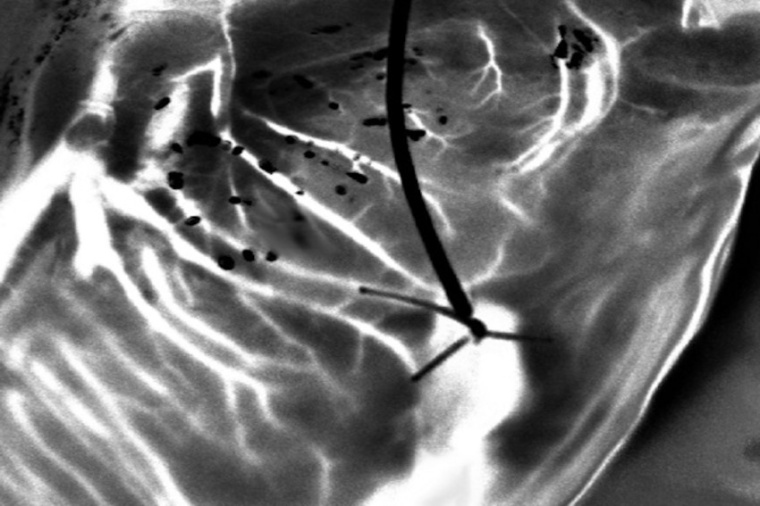

The method utilizes a recently developed speckle imaging technique – Laser Speckle Orthogonal Contrast Imaging (LSOCI), that was developed to detect the multiple scattering of moving red blood cells. In this study, the researchers improved the imaging capability of LSOCI to observe small blood vessels in the heart. The proposed method thus analyzes blood flow in the heart using a specific polarimetric filtering process that allows suppression of surface scattering. Thus, the time varying speckle patterns used for the imaging process are mainly generated by multiple scattering on moving red blood cells inside peripheral vessels. “The optical technique allows high-resolution imaging of the entire peripheral vasculature of the heart in real time,” says Colin.

To test this method, the researchers developed a clinical model to study coronary circulation on donor hearts before transplantation. They then used a laser and a camera mounted on an articulated arm fixed above the perfusion module – which contained the donor heart – to generate and analyze rapidly varying speckle patterns. To overcome the challenges in tracking vasculature due to the beating of the heart, the researchers further optimized the technique with the method of multi-period-enhanced signal-to-noise ratio (MPE-SNR). They took a series of images over time to build a set of frames that depicted the vasculature at similar heart positions. Each image in this sequence was then optimized using the other images to reduce noise and enhance details. The optimized image represented the vasculature at a different time point, and the researchers used a sequence of such images to visualize vasculatures as small as 100 microns in a few seconds.